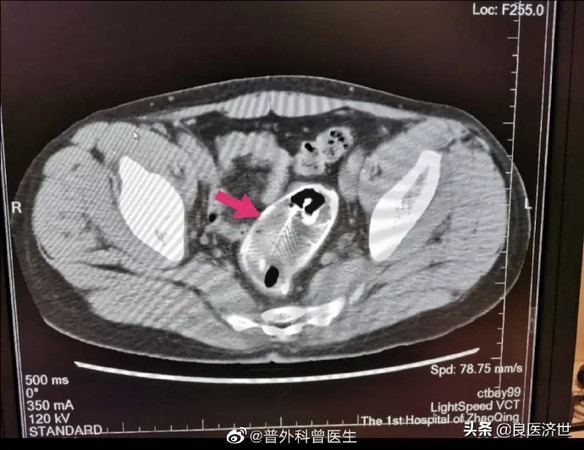

醫院給他做了X光掃描,一照之下發現這條吳郭魚非常大,本來想要用內視鏡夾出,卻發現魚頭最寬的地方竟有3公分,魚鰭的刺還弄傷腸壁,醫生研判無法直接取出,只好開腹拿出。